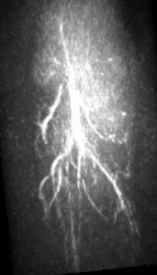

The maximum intensity projection (MIP) of the 3D mouse images reconstructed by use of the GPU-based implementations reveal the mouse body vasculature as shown in Fig. 7. Images reconstructed by use of both the PLS-Int and the PLS-Sph algorithms appear to have cleaner background than do the images reconstructed by use of the FBP algorithm from the same amount of data. All images reconstructed by iterative algorithms were obtained by 202020-iterations starting with uniform zeros as the initial guess. The PLS-Int algorithm took approximately a half day and 222 days to process the “quarter data” and the “full data” respectively. The PLS-Sph algorithm took approximately one day and 444 days to process the “quarter data” and the “full data” respectively. Alternatively, if the CPU-based implementations were utilized, the PLS-Int algorithm would take an estimated 686868 days and 277277277 days to process the “quarter data” and the “full data” respectively. The PLS-Sph algorithm would take an estimated 275275275 days and 1,10011001,100 days to process the “quarter data” and the “full data” respectively.